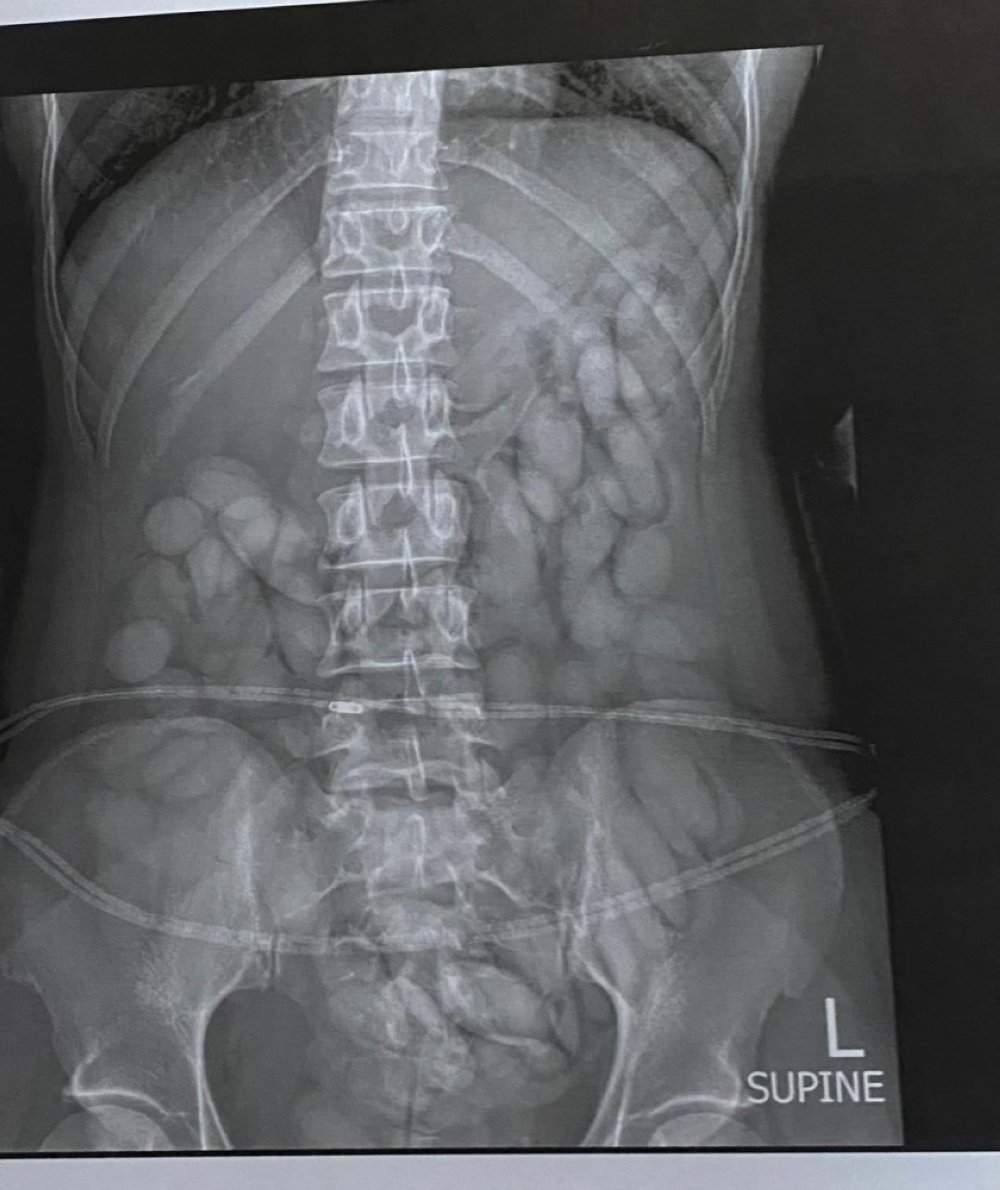

Unfortunately Paulina Mbangula was detected to have strange substance in her stomach by airport X-ray body reader and she was taken to the nearest hospital to extract all the drugs out of her stomach.